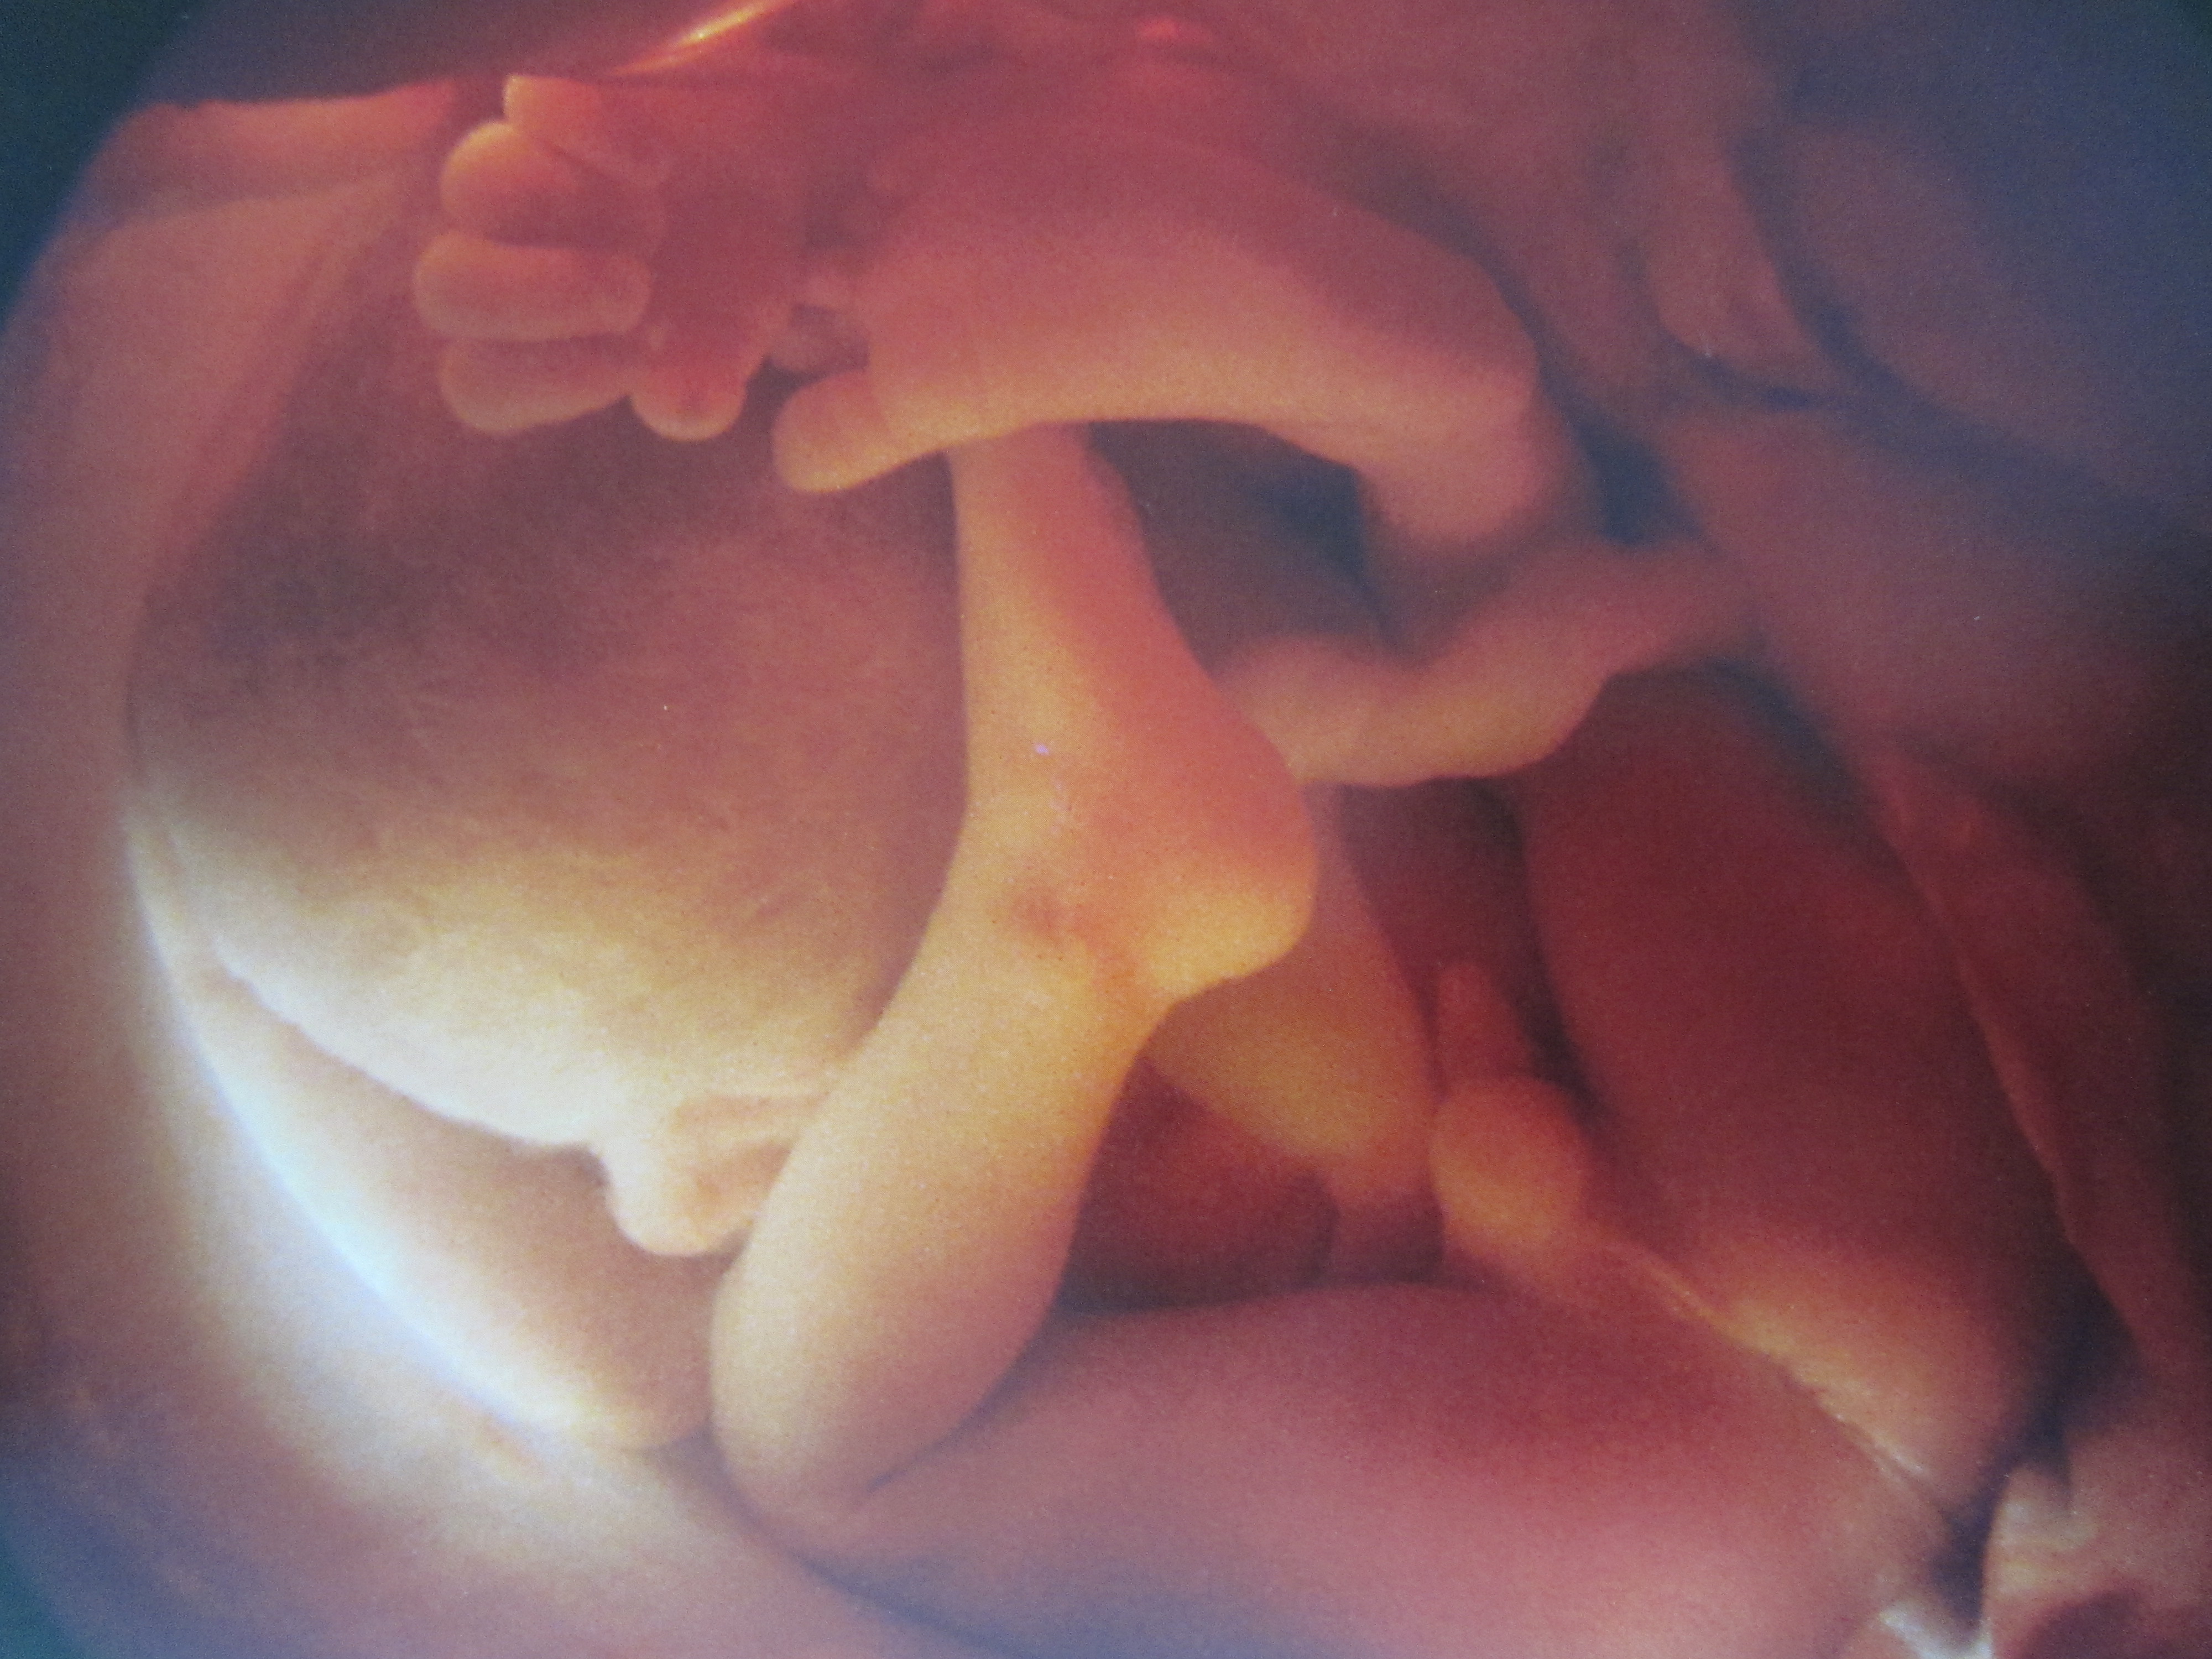

Развитие плода на 32-ой неделе: вес размер и пол

К этой неделе малыш подрос до 43 см в длину и набрал около 1800 г веса, но могут быть колебания веса за счет конституциональных особенностей и течения беременности. Сейчас происходит активный рост малыша, именно за счет его прибавок веса и происходит прибавка веса самой мамы, плюс немного на свои нужды. Сейчас все его органы и системы активно работают и тренируются к самостоятельной жизни, а нервная система созревает и формирует все новые и новые связи и рефлексы. Постоянно происходит совершенствование и регулировка работы эндокринных желез – гипофиз активно руководит щитовидной, поджелудочной железами и надпочечниками, которые выделяют необходимые плоду гормоны для роста и развития. За счет этих гормонов происходит обмен веществ и рост новых клеток. Активно работает и иммунная система плода, за счет ее работы происходит синтез антител, которые будут защищать ребенка в первые несколько месяцев после рождения.

Ребенок уже сильно изменился и внешне с предыдущих недель – кожа разглаживается, она становится розового цвета, за счет отложения подкожного жира округляются ручки и ножки, становятся круглыми щечки. Постепенно с тела исчезает пушок (лануго), волосики на головке ребенка становятся темнее и плотнее, но они все еще редкие и мягкие. В этом сроке положение плода в матке уже становится стабильным, и в нем он, скорее всего, останется уже до родов. Только в редких случаях тазового предлежания в этом сроке ребенок а счет определенных положений матери и гимнастики может развернуться вниз головой. Чаще всего, он остается в тазовом предлежании, и для вас решается вопрос о дальнейшем ведении родов.

Костная ткань ребенка совершенствуется, его скелет накапливает кальций, но кости черепа еще очень мягкие, между ними расположены большие швы, за счет которых головка сможет продвигаться по родовым путям матери во время его рождения. Мышцы и связки все сильнее укрепляются, что делает движения малыша все сильнее, и каждое шевеление мама чувствует очень отчетливо. Теснота матки приводит к тому, что ребенок занимает позу эмбриона, приводя ножки и ручки к животу и иногда вытягивая их и распрямляя. Учитывая, что он упирается ножками под ребра, порой его движения даже болезненны. Сейчас у ребенка уже примерно сформирован режим сна и бодрствования, когда он спит, его шевеления незначительны, а вот в период активности он может давать о себе знать резко и сильно. Малыш почти созрел для самостоятельной жизни, активно дозревают его дыхательная система и легкие, а также постоянно совершенствуется кора головного мозга. На этой неделе, если он родится, он сможет уже вполне громко плакать, его зрение достаточно развито, хотя он еще близорук, но зрачки отлично реагируют на свет. Также он отлично слышит и реагирует на голоса матери и отца, чувствует прикосновения и поглаживания, отвечая на них толчками. Он уже видит сны и запоминает происходящие с ним события.